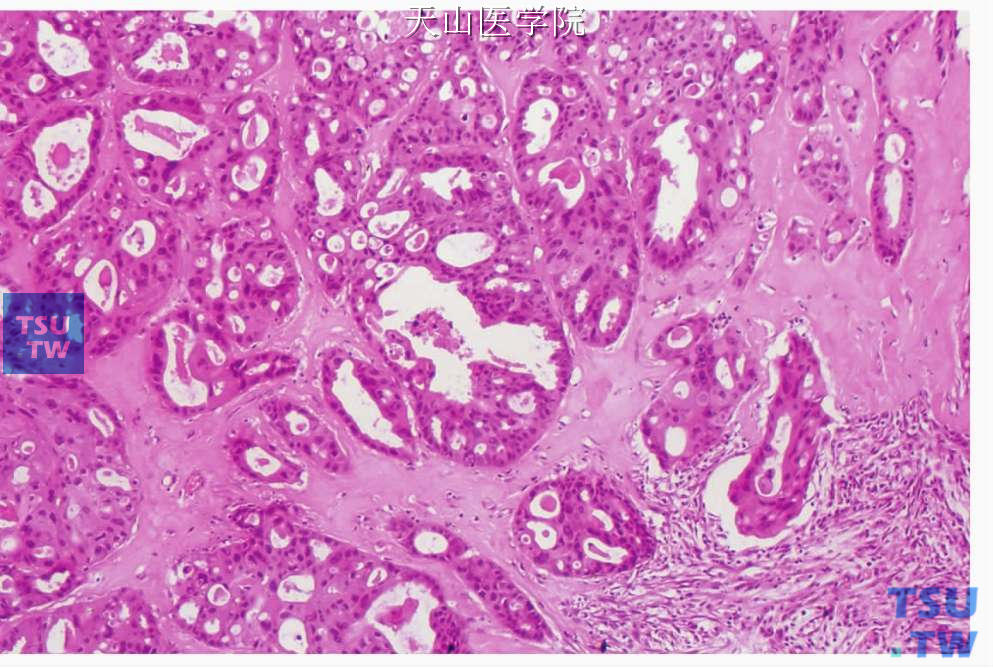

唾液腺导管癌(salivary duct carcinoma,SDC)是类似于乳腺高级别导管癌的少见的高度恶性的肿瘤,Kleinsasser等1968年首先报告,其组织结构与乳腺发生的导管癌极为相似,以多灶性界限